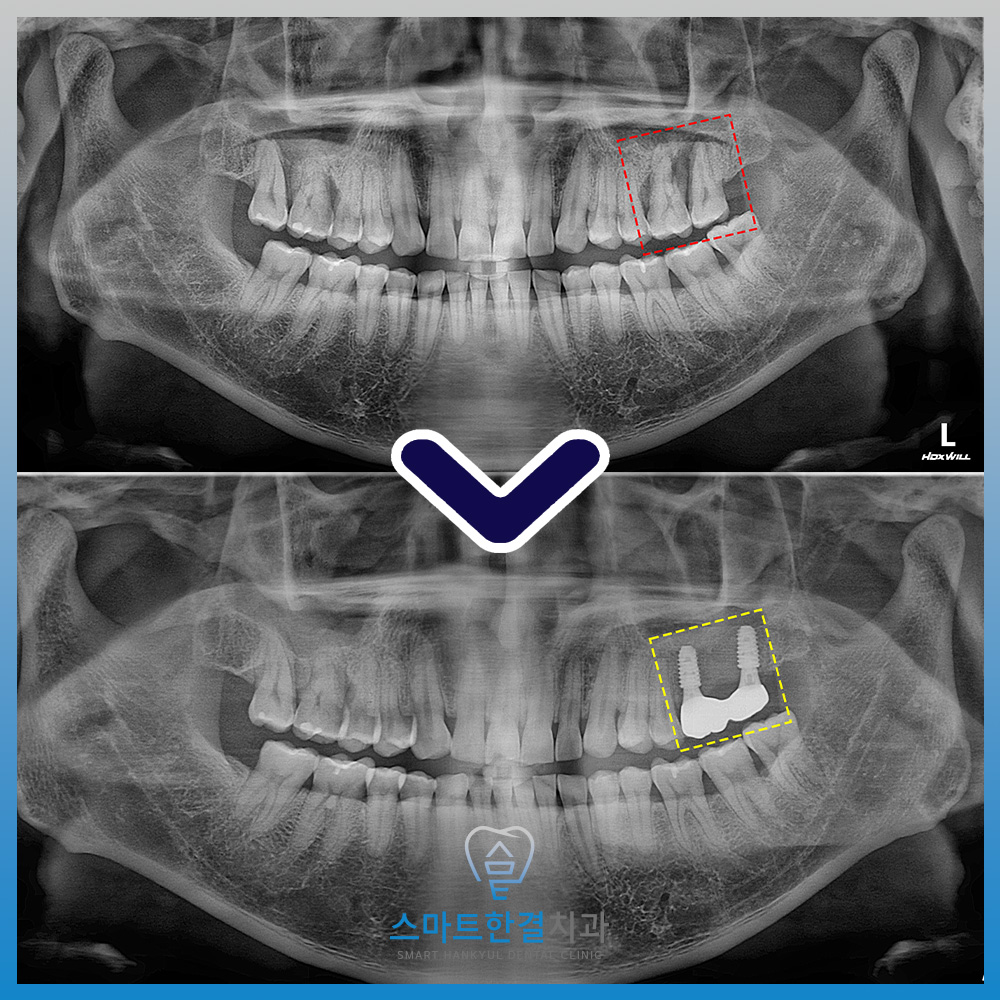

화서동치과 스마트한결의

치료 전후 사진이에요.

염증 없이 깨끗하게

임플란트가 마무리 된게 보이시나요?

환자분께서는 식사할 때마다

불편함이 있어 오른쪽으로만

식사하시던 상황이었고,

오른쪽도 문제가 생길까

걱정하셨는데요.

그러나 치료 후,

이제는 양쪽으로 골고루 씹으며

식사할 수 있게 되어

매우 만족하셨어요.